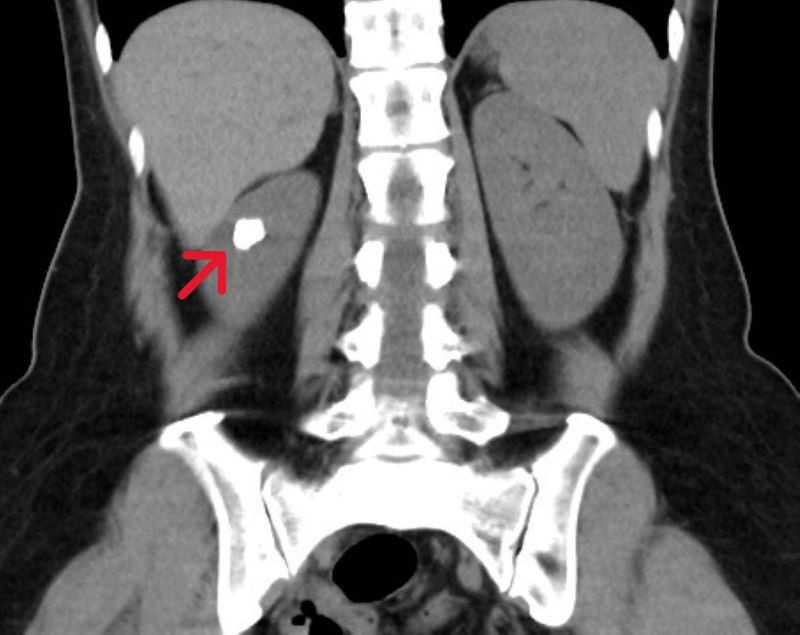

電腦斷層影像中,可見田女士左側腎臟的結石集合體嵌在憩室內。

50歲的田女士天生患有腎盞憩室並伴隨結石,但因擔心傳統開刀手術的傷口與復原期,多年來僅在住家附近的診所定期追蹤。直到近期頻繁受到泌尿道感染困擾,嚴重影響生活品質,才轉至台北慈濟醫院就診。泌尿科鐘伯恩醫師經電腦斷層檢查發現,田女士左側腎臟內約有1.5公分的結石群嵌在腎盞憩室中,而憩室與正常腎盞之間的通道僅不到1毫米,導致尿液排出不良並形成結石。手術時先以具止血效果的雷射切開並擴大憩室狹窄的通道,接著以「負壓吸引鞘與軟式輸尿管鏡碎石手術」將結石擊碎並同步吸出,放置雙J導管維持通道通暢直至傷口定型後取出,以降低日後再次狹窄及尿液滯留的風險。術後田女士恢復良好,隔日即順利出院,成功解決多年來的結石與反覆感染問題。